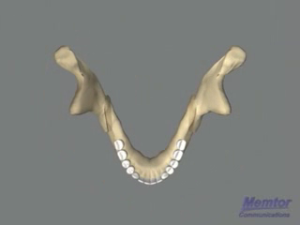

Recul mandibulaire - Vue osseuse 2